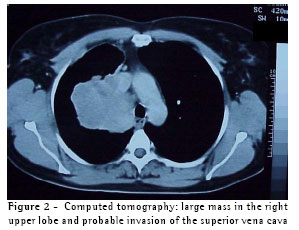

upper lobe (caused by occlusion of the upper lobe bronchus) that extended up to the juxtacarinal portion of the main bronchus, accompanied by infiltration of the wall of the main left bronchus, which resulted in invasion of the right branch of the pulmonary artery and of the arch of the azygos vein. There was no sign of invasion of the chest wall or of pleural effusion (Figure 2). Tomographic findings led us to suspect invasion of the superior vena cava and azygos vein. Therefore, we performed a cavography, which did not reveal any involvement of these structures (Figure 3).